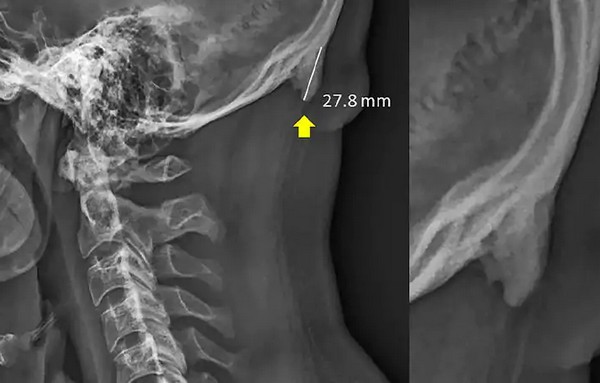

పొద్దస్తమానం స్మార్ట్‌ఫోన్‌తోనే గడుపుతున్నారా? ముఖ్యంగా, గంటల కొద్ది తలవంచి స్మార్ట్‌ఫోనునే చూస్తున్నారా? అయితే, మీ పుర్రె వెనుక భాగంలో కొమ్ములు వచ్చివుంటాయి. ఓసారి వైద్యుడిని సంప్రదించి చెక్ చేయించుకోండి. లేదంటే ప్రాణాపాయం తప్పదు. ఈ మాట అంటున్నది ఎవరో కాదు.. ఆస్ట్రేలియా పరిశోధకులు.

గంటల కొద్దీ స్మార్ట్ ఫోన్ చూసేందుకు మెడ భాగాన్ని అలా ఎక్కువసేపు వంచి ఫోన్‌ తెర వైపే చూస్తూ గడపడం వల్ల.. అక్కడి కండరాలపై అదనపు ఒత్తిడి పడి.. పుర్రె వెనుక దిగువ భాగంలో ఎముక పెరుగుతోందని (బోన్‌ స్పర్స్‌) ఆస్ట్రేలియా పరిశోధకులు హెచ్చరిస్తున్నారు. శాస్త్రజ్ఞులు వీటిని 'ఎంథియోసోఫైట్స్'గా పేర్కొంటున్నారు.